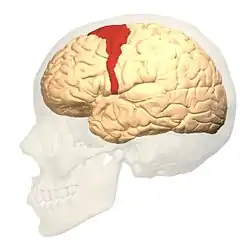

Kora ruchowa

Kora ruchowa – obszar kory mózgu odpowiedzialny za planowanie i wykonywanie ruchów dowolnych ciała. Znajduje się w płacie czołowym.

Pierwszorzędowa kora ruchowa

Pierwszorzędowa kora ruchowa (ang. primary motor cortex, MI) leży w zakręcie przedśrodkowym płata czołowego mózgu (w obszarze odpowiadającemu polu 4 Brodmanna). Charakteryzuje się dobrze rozwiniętą V warstwą, w której znajdują się duże neurony piramidowe zwane komórkami Betza. Ich bardzo długie aksony biegną drogami piramidowymi do ośrodków ruchu w rdzeniu kręgowym, gdzie tworzą połączenie z motoneuronami unerwiającymi mięśnie.

Pierwszorzędowa kora ruchowa jest silnie połączona z pozostałymi obszarami kory ruchowej. Otrzymuje też bogatą informację z pierwszorzędowej kory czuciowej, zlokalizowanej w zakręcie zaśrodkowym płata ciemieniowego.